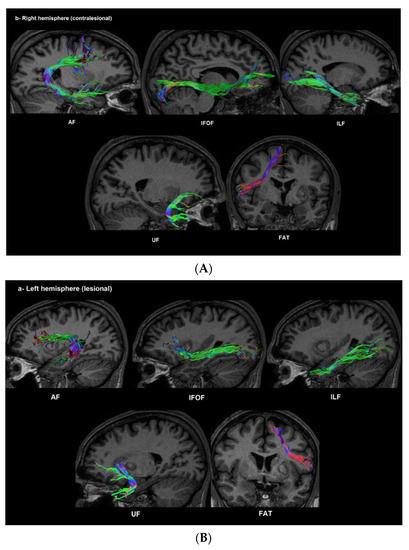

3.3. Diffusion Data

3.4. Correlation between Changes in DTI Measures and Behavioral Improvement